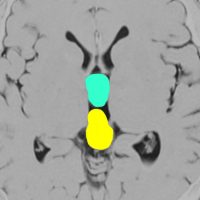

20代の女性に偶然見つかったものです。水色に塗ったのが鞍上部クモ膜のう胞 arachnoid cyst,黄色に塗ったのが松果体のう胞 pineal cystです。両方ともとても珍しもので,大きなのう胞です。クモ膜のう胞と松果体のう胞が同じ原因で形成されることを示唆しています。